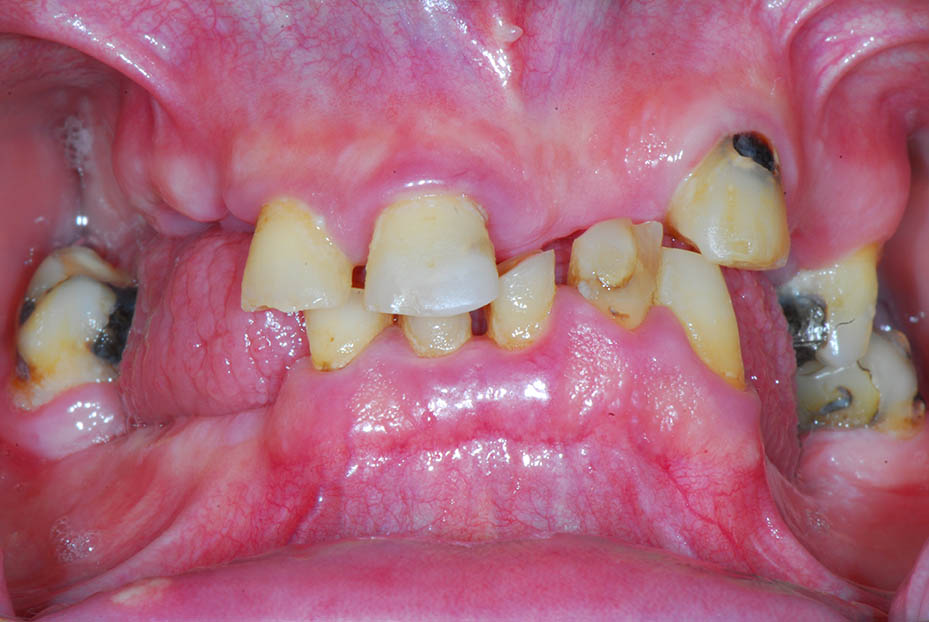

Full mouth implant reconstruction with an upper full arch zirconia bridge supported on six implant fixtures, and a lower full arch titanium framework acrylic bridge, also on six implant fixtures.

Before